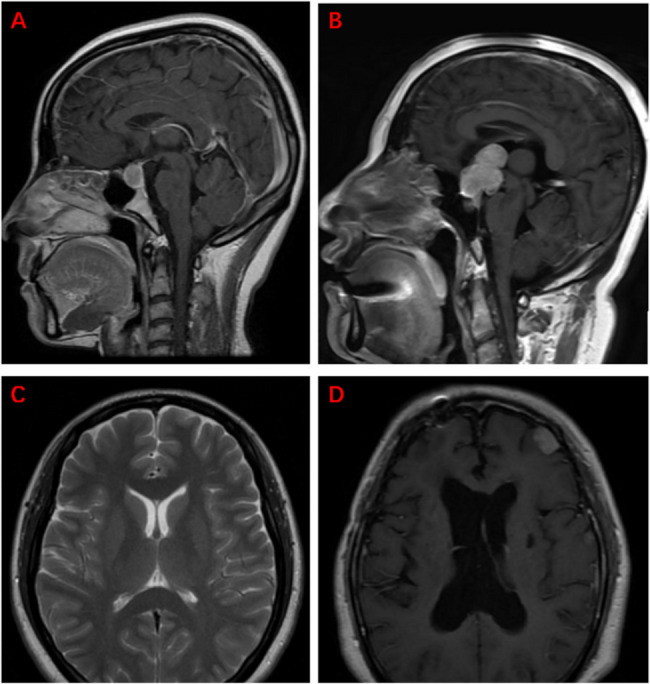

Methods: We screened patients who had undergone TSS for PitNETs at a single center to identify those who did and did not (control) develop sodium imbalance. Disorders were classified using three groups, based mainly on the serum sodium level and degree of daily increase or decrease therein. We performed multivariable logistic regression analysis to identify risk factors among numerous variables (patient characteristics, third ventricle deformation, tumor volume, maximum tumor diameter, hydrocephalus, cerebrospinal fluid rhinorrhea, and pituitary target gland axes).

Results: The sample comprised 105 patients with and 129 patients without sodium imbalance. Logistic regression analysis showed that hydrocephalus [P = 0.0015, odds ratio (OR) = 7.112, 95% confidence interval (CI) 1.475-34.3], cerebrospinal fluid rhinorrhea (P < 0.001, OR = 4.62, 95% CI 2.372-9), and preoperative hypothalamus-pituitary-gonadal (HPG) axis hypofunction (P = 0.009, OR = 3.211, 95% CI 1.341-7.691) were independent risk factors sodium imbalance development after TSS. Compared with the control, risk factors differed among disorder groups.